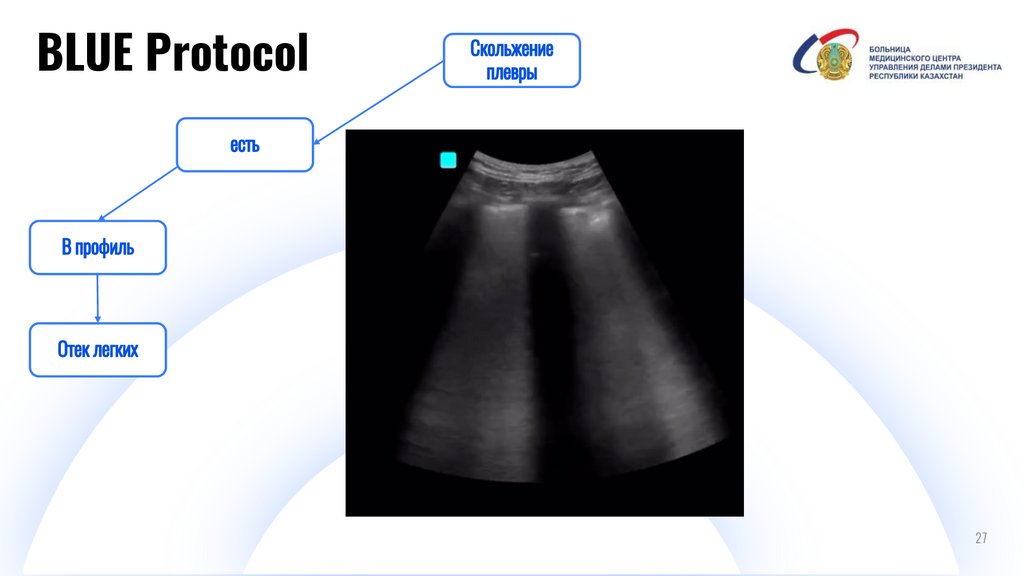

BLUE Protocol

И

Digital IT pitch-deck PowerPoint bundle

27